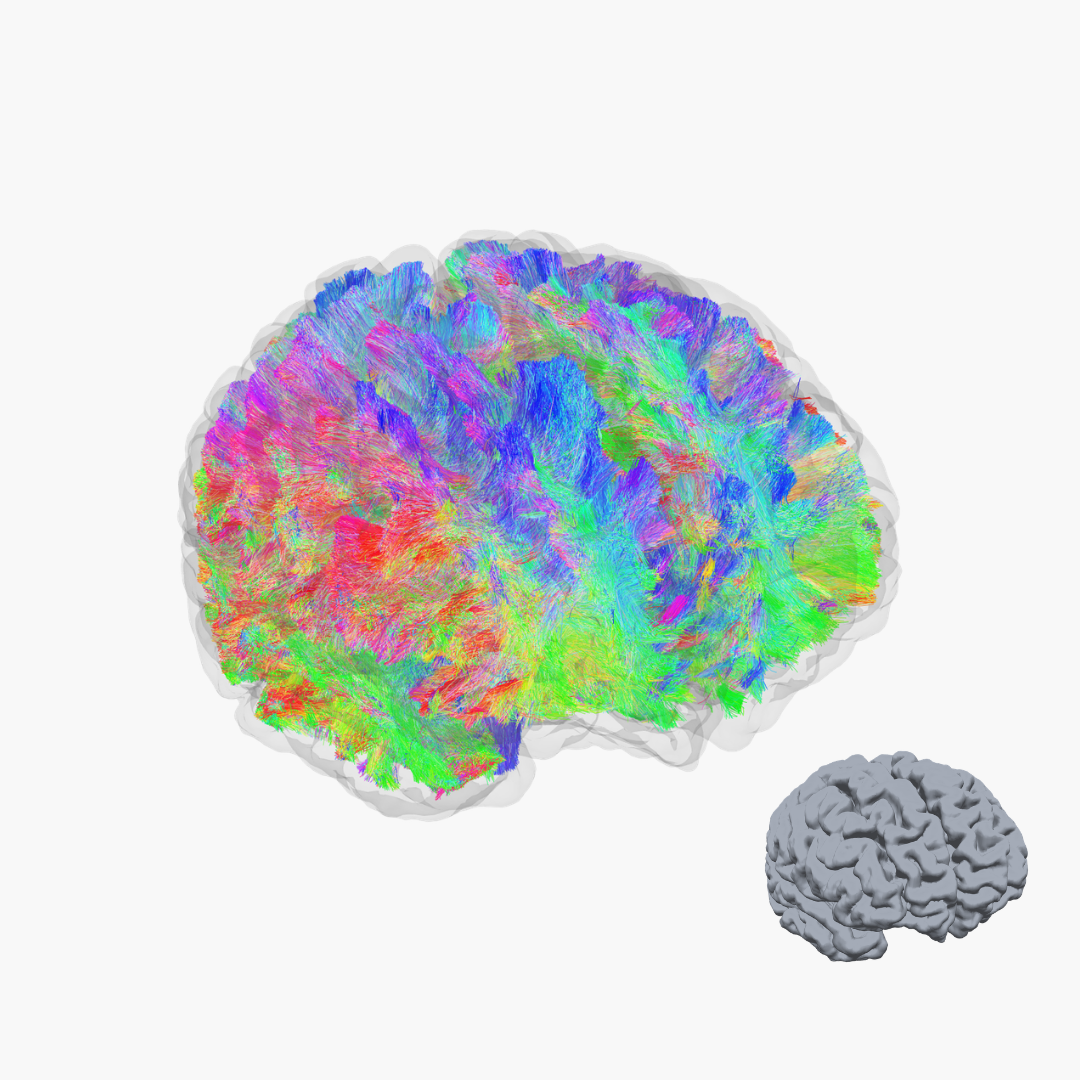

Die strukturelle MRT und Traktographie machen die feinen Nervenfaserbahnen (weiße Substanz) sichtbar, die für eine gesunde Funktion des Gehirns entscheidend sind.

Unser Ziel ist es, funktionelle und strukturelle Bildgebungsverfahren gezielt zu nutzen, um eine möglichst präzise Diagnostik zu ermöglichen und so die Grundlage für fundierte therapeutische Entscheidungen zu schaffen. Durch die Kombination aus hochauflösender MRT, funktioneller Bildgebung (fMRT) und Traktographie erhalten wir ein detailliertes Verständnis sowohl der anatomischen Strukturen als auch der funktionellen Abläufe im Gehirn.